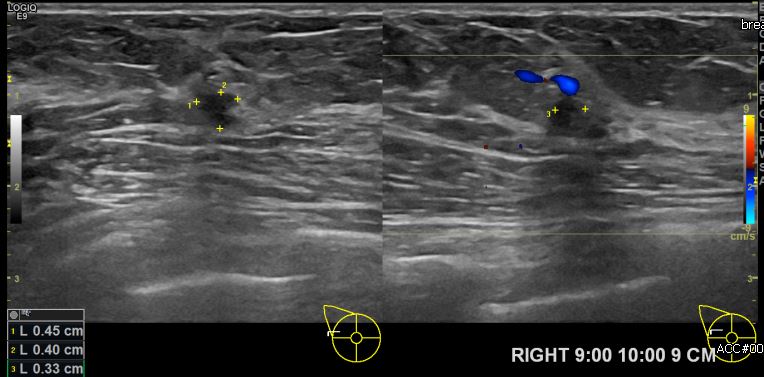

유방에 멍울과 통증으로 내원하신 30대 여성분으로 우측 9시에서 10시 방향에서 9cm    떨어진 거리의 으심스러운 멍울 조직검사 시행하여  우측 침윤성 유관암 진단되었습니다.